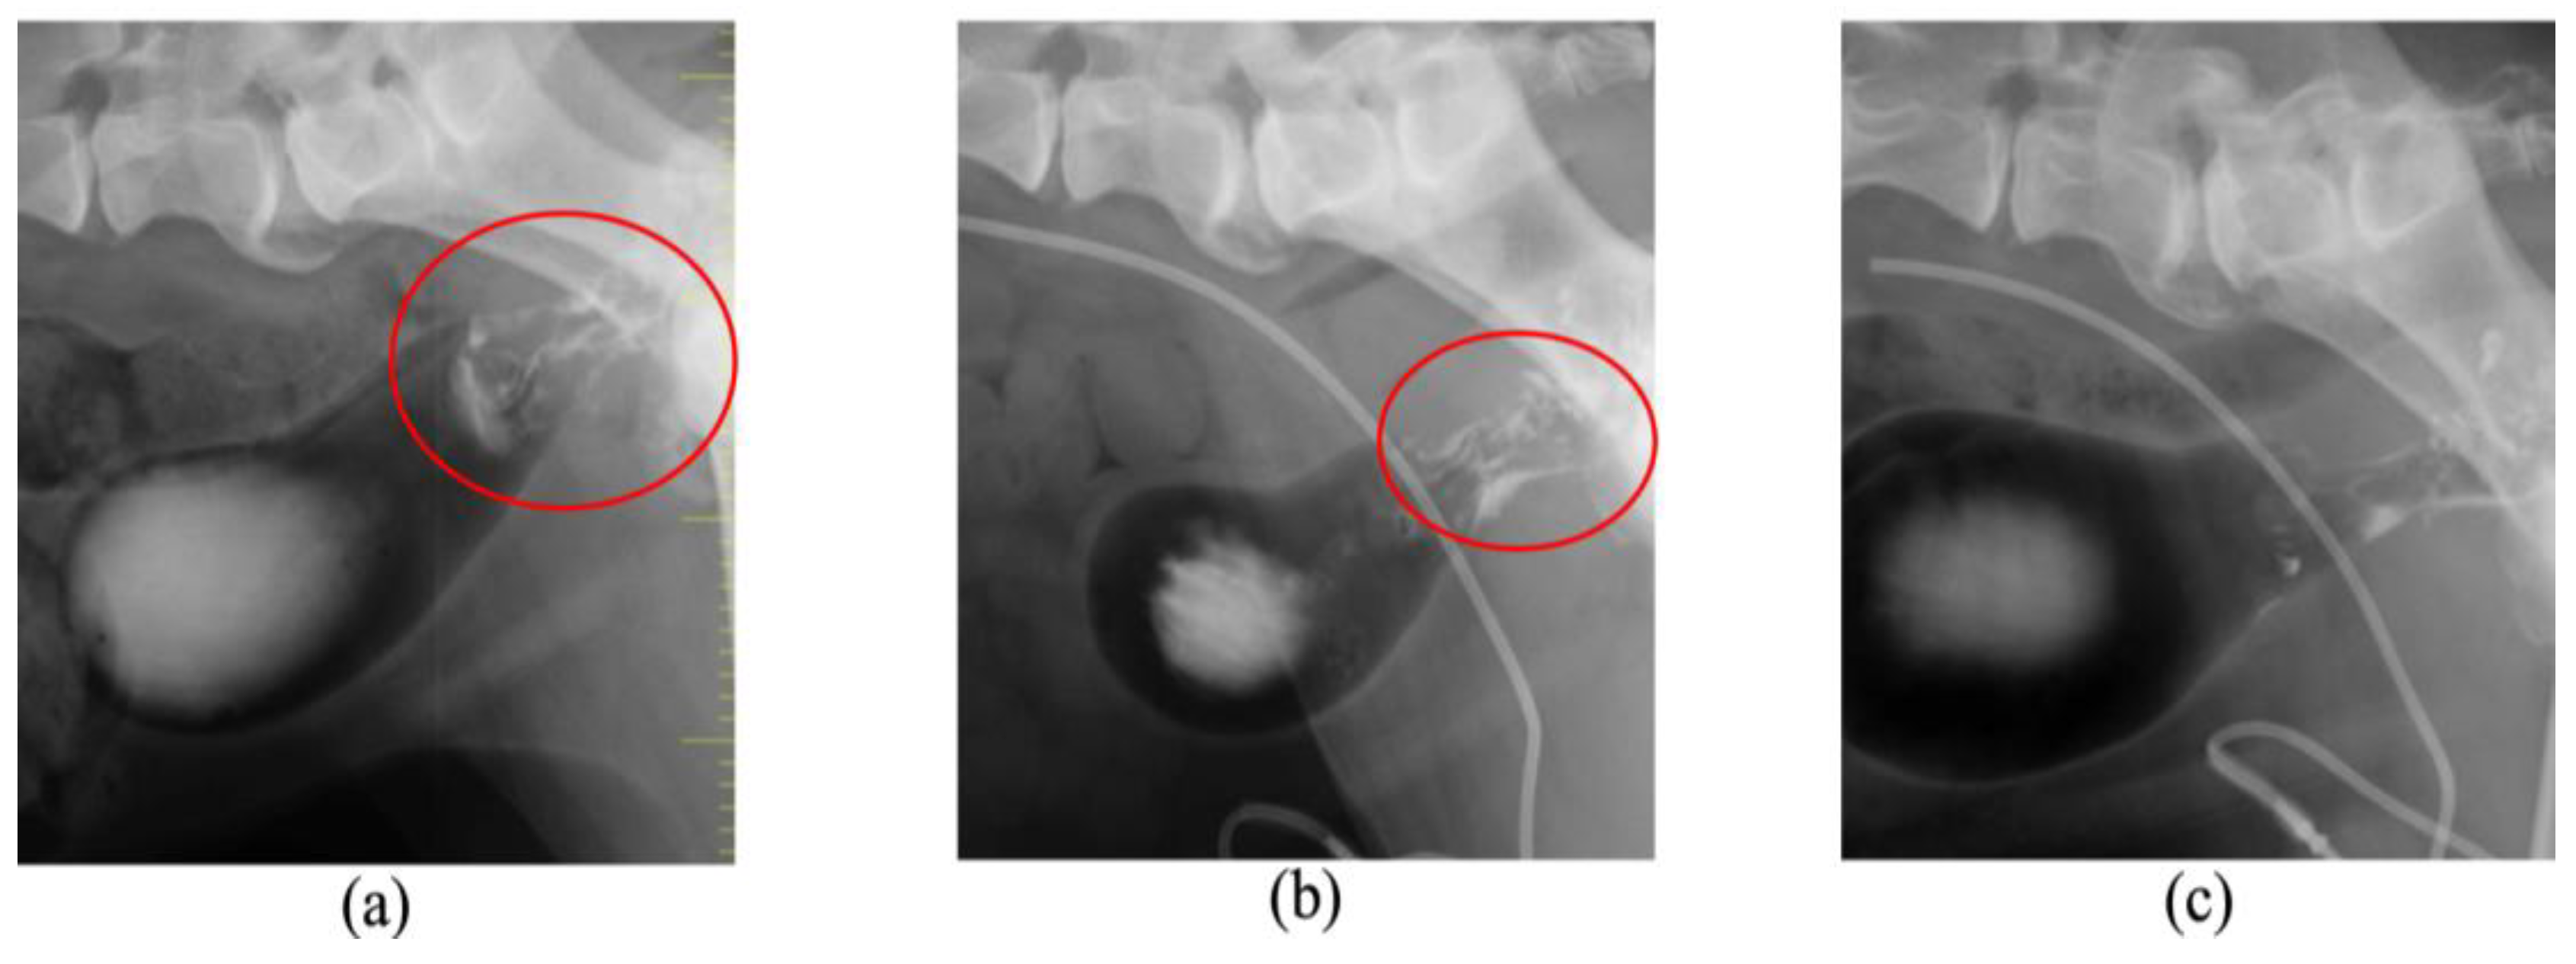

| 3 | Dog | Chihuahua | 12 | SF | 2.8 | Transitional cell carcinoma | Nasal cavity | + | |

| 3 | LED | 200 | 300 | 3 | PR | 75 | PDT with another PS 6 | ||